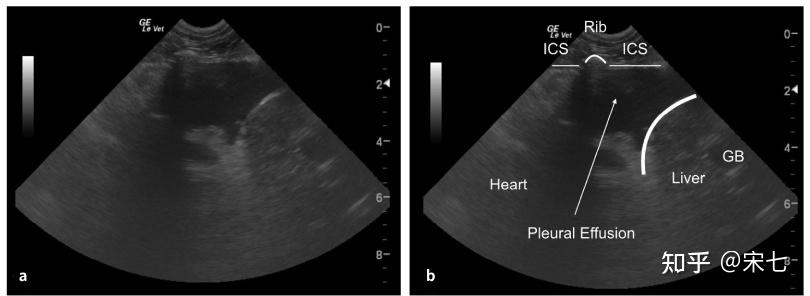

猫传腹(fip)的影像诊断